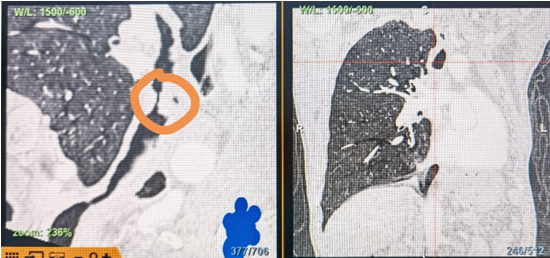

時間就是生命!了解患者病情后,歐陽海峰立刻啟動氣道梗阻緊急救治通道,協(xié)調(diào)院前轉(zhuǎn)運,急診快速入院流程。凌晨患者入院胸部CT顯示,現(xiàn)存唯一的呼吸通道在右主支氣管處,狹窄處僅約3毫米,患者命懸一線!

運用呼吸介入技術(shù),軟硬鏡結(jié)合快速開通氣道,是患者目前唯一可行的治療方案,手術(shù)刻不容緩!但存在麻醉后氣道完全塌陷閉合、大出血、窒息等巨大風(fēng)險。患者此前接連轉(zhuǎn)診3家醫(yī)院,均建議保守支持治療或轉(zhuǎn)院。歐陽海峰詳細了解患者病史,全面評估影像檢查結(jié)果后,決定盡快進行手術(shù),組織醫(yī)護團隊對患者進行持續(xù)密切監(jiān)測,充分保障其術(shù)前安全。